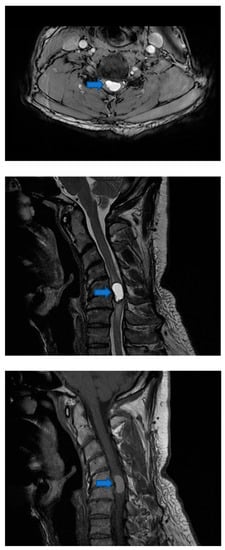

2.1. Pre-Surgical Intervention Imaging